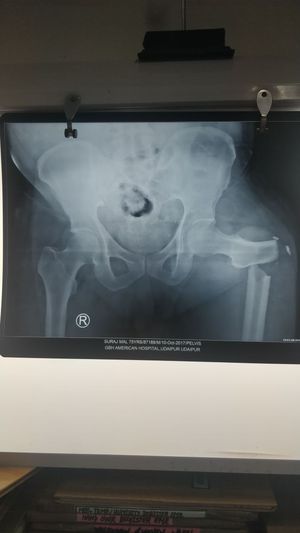

Fracture

Fracture as a result of fall from stairs.